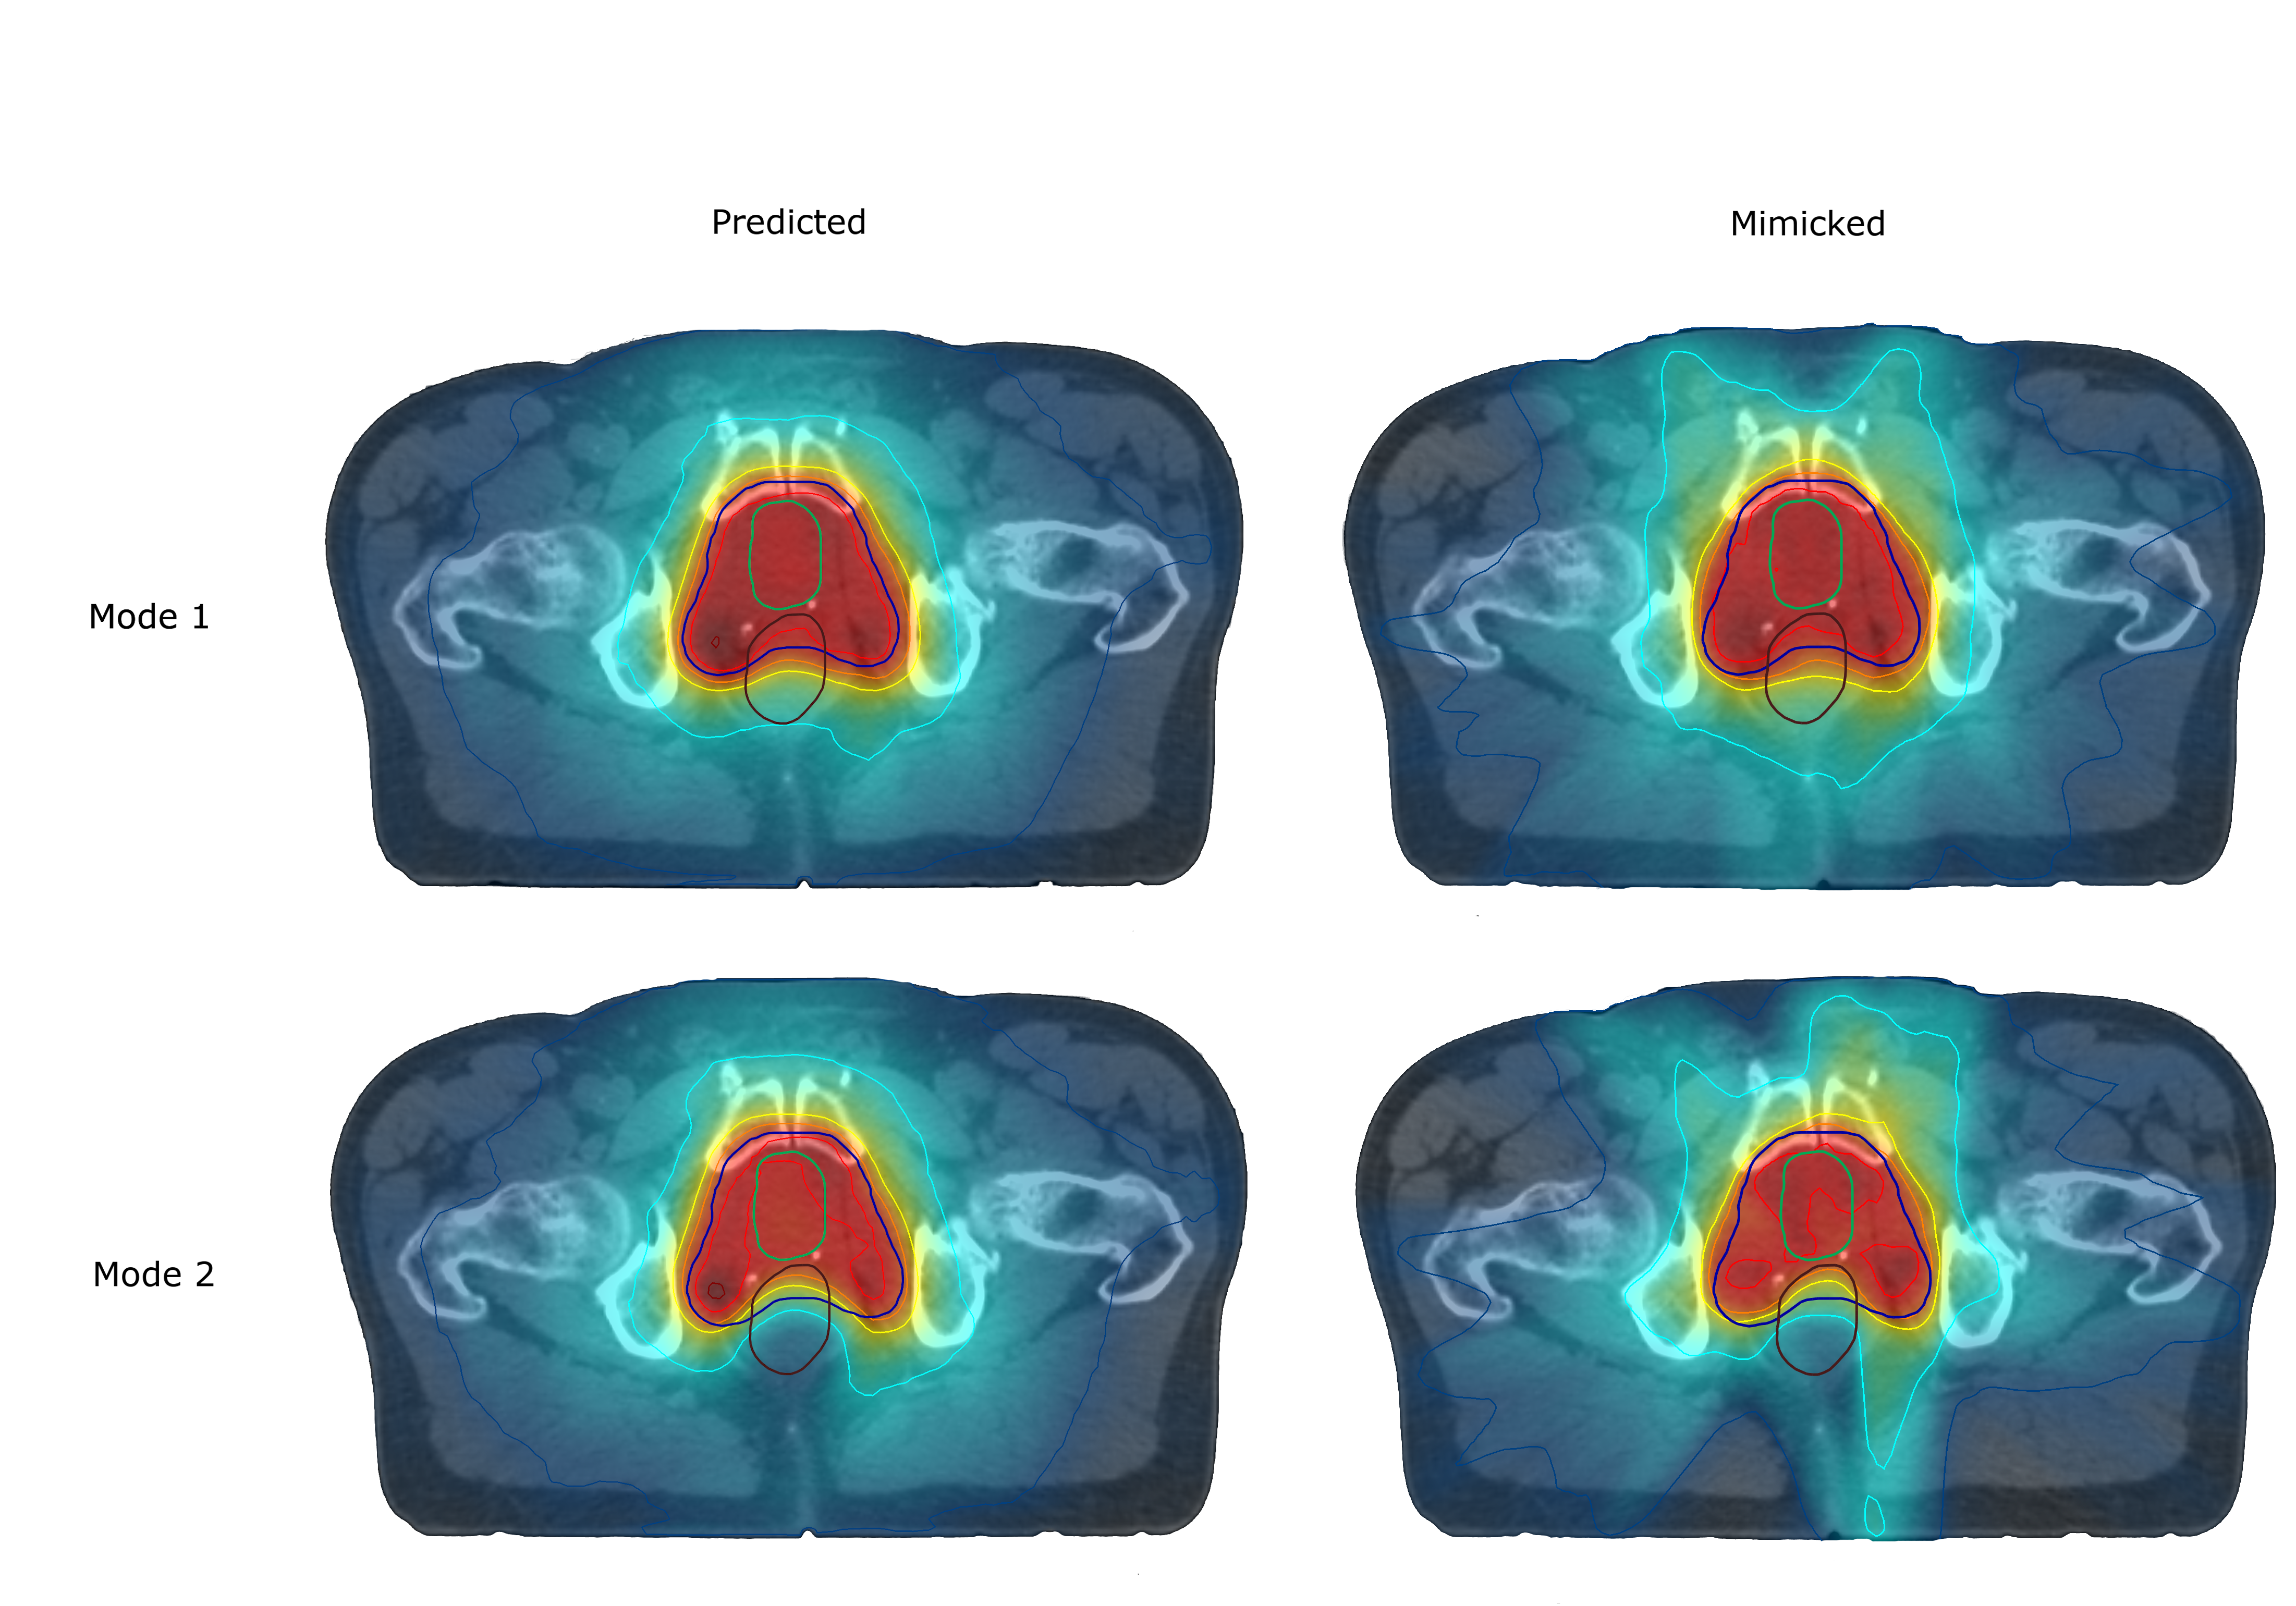

In this work, the training data consisted of a pair P1subscript𝑃1P_{1}, P2subscript𝑃2P_{2} of treatment plans created for each patient, where P2subscript𝑃2P_{2} has a dose distribution that spares the rectum to a higher extent than P1subscript𝑃1P_{1}, in general at the cost of sacrificing target coverage. In figure 3, one can see the dose distributions for each such plan in a transverse cross section for a representative patient. The training data was generated by application of an ML-based dose prediction and dose mimicking optimization using RayStation 9A (RaySearch Laboratories, Stockholm, Sweden). The ML algorithm used to predict the doses was trained on approximately 100 clinical plans and is based on the method provided in [19]. The model used to create the training data was configured to predict one plan P1subscript𝑃1P_{1} that prioritizes target coverage and another plan P2subscript𝑃2P_{2} that prioritizes sparing of the rectum area. By applying this planning process for 16 patients from the Iridium dataset, 32 plans were created for the training dataset. The objective of using this dual input of plans for each patient is that one can easily validate that this twofold dose preference in the rectum is reflected in new MDN predictions. Rather than creating two clinically acceptable plans, P1subscript𝑃1P_{1} and P2subscript𝑃2P_{2} just reflect two different planning protocols.

Refer to caption

Figure 3: Example of doses used for training. The slice of dose to the left represents the target coverage plan P1subscript𝑃1P_{1} and the right one the the spare rectum plan P2subscript𝑃2P_{2}. The slices are from the same patient and position on the longitudinal axis.